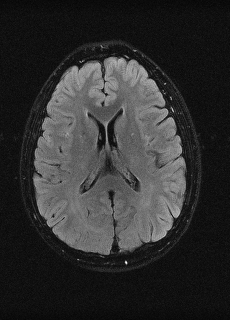

As we observe from the right image in Fig. 2, our BRM, both from MIMO and SISO settings, predicts the performance of dedicated models with a high correlation. We further choose the best three , and perform the last stage of fine-tuning accordingly to (6). A visual evaluation on real data is shown in Fig. 3. For simulated data, please refer to the Supplemental Material section.

Base on the best performing , we perceive that among , , and FLAIR, the results are best when is sampled the most. We suggest that this makes intuitive sense as images provide the best contrast out of the three sequences, which can compensate for the details lost in other images. The same observation can be made on the simulated data, where both and FLAIR show good contrast. When the time setting is changed to non-uniformity, we can see that our search for the best sampling strategy reflects the change. is sampled more as a result of faster acquisition time, while is still sufficiently sampled.

| Sequence | LR | SISO | MIMO | MIMO tuned | GT |

|---|---|---|---|---|---|

(a) 34.38/0.9371

(a) 34.38/0.9371

|

(b) 42.42/0.9883

(b) 42.42/0.9883

|

(c) 44.60/0.9920

(c) 44.60/0.9920

|

(d) 45.50/0.9940

(d) 45.50/0.9940

|

(e) PSNR/SSIM

(e) PSNR/SSIM

|

|

(f) 29.74/0.8903

(f) 29.74/0.8903

|

(g) 36.25/0.9734

(g) 36.25/0.9734

|

(h) 36.42/0.9752

(h) 36.42/0.9752

|

(i) 37.70/0.9832

(i) 37.70/0.9832

|

(j) PSNR/SSIM

(j) PSNR/SSIM

|

|

(k) 39.89/0.9311

(k) 39.89/0.9311

|

(l) 43.94/0.9864

(l) 43.94/0.9864

|

(m) 44.74/0.9883

(m) 44.74/0.9883

|

(n) 45.49/0.9894

(n) 45.49/0.9894

|

(o) PSNR/SSIM

(o) PSNR/SSIM

|